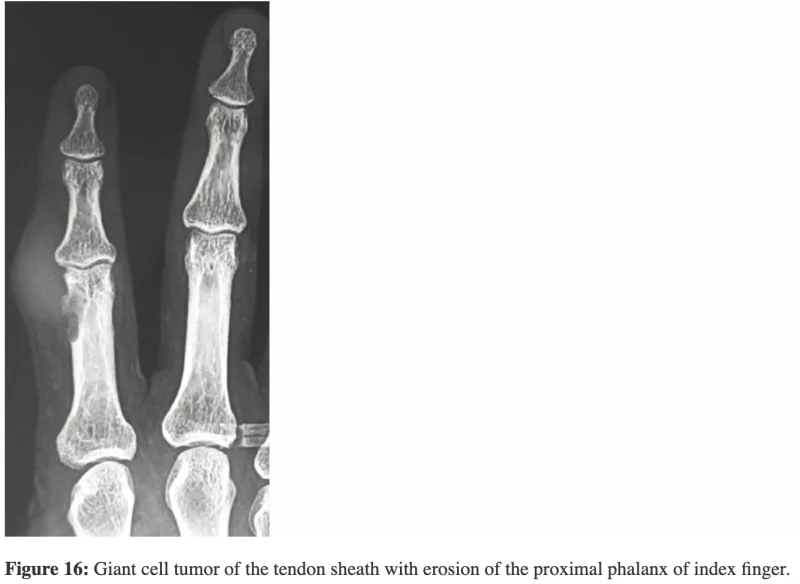

腱滑膜巨細胞腫は大きくなると骨を溶かして, 食い込むように増殖します.

引用元:Kakarla S. Tumoral lesions of the bones of the hands – Pictorial essay. J Med Sci Res. 2018. 6.

骨に食い込むほど大きくなった腫瘍でした.